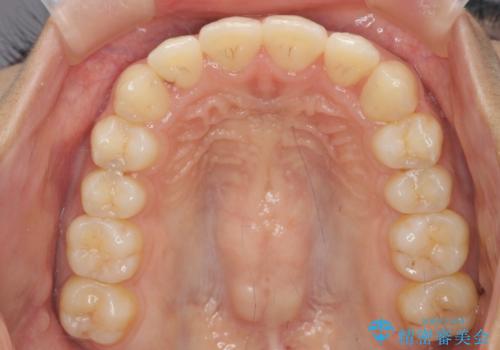

- 前歯のガタつき、上下たがい違いになっている歯並び(クロスバイト)の改善を求めて来院されました。

上下すれ違った噛み合わせはマウスピースでは改善に時間がかかり、またねじれが残ってしまうことも多々見られます。

マウスピース矯正を行う前に、これらの症状の改善の得意なワイヤー部分矯正を行うことで治療期間を短縮し、確実にすれ違いを改善することができます。